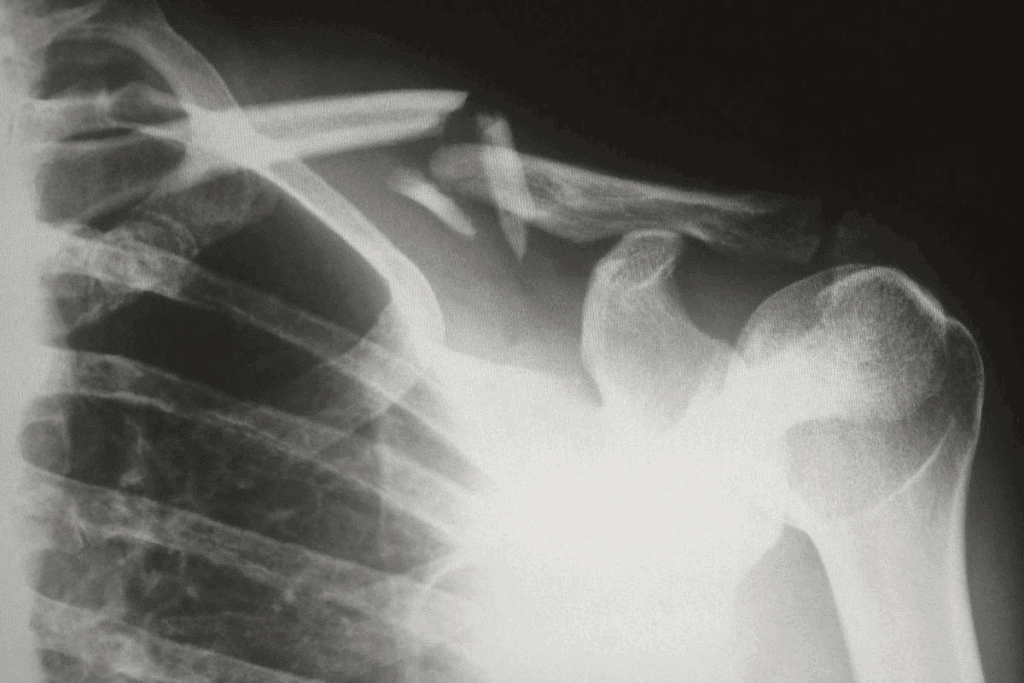

Fracture Healing in Young vs. Older Adults

Young people heal bones faster than older adults. Younger bodies have more cells and a better blood supply. Older adults heal slower because of these changes.

Key differences in fracture healing between young and older adults include:

- Reduced cellular activity: Older adults have fewer cells available for bone repair.

- Decreased growth factor production: Growth factors essential for bone healing are produced at lower levels in older adults.

- Impaired blood supply: Aging can lead to reduced vascularity, affecting the delivery of nutrients and cells necessary for bone repair.